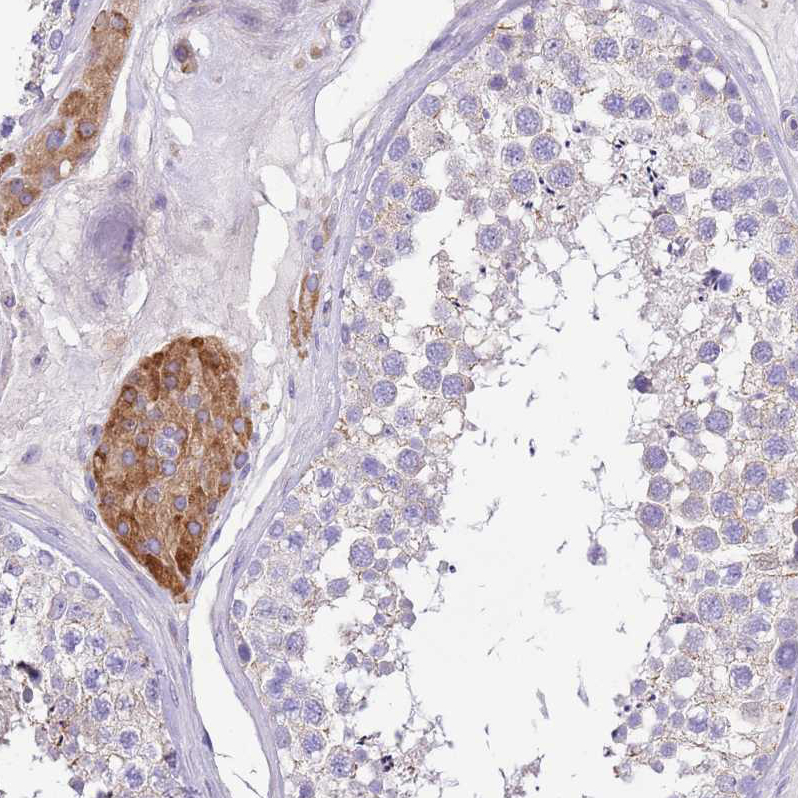

Immunohistochemical staining of human testis shows strong granular cytoplasmic positivity in Leydig cells.